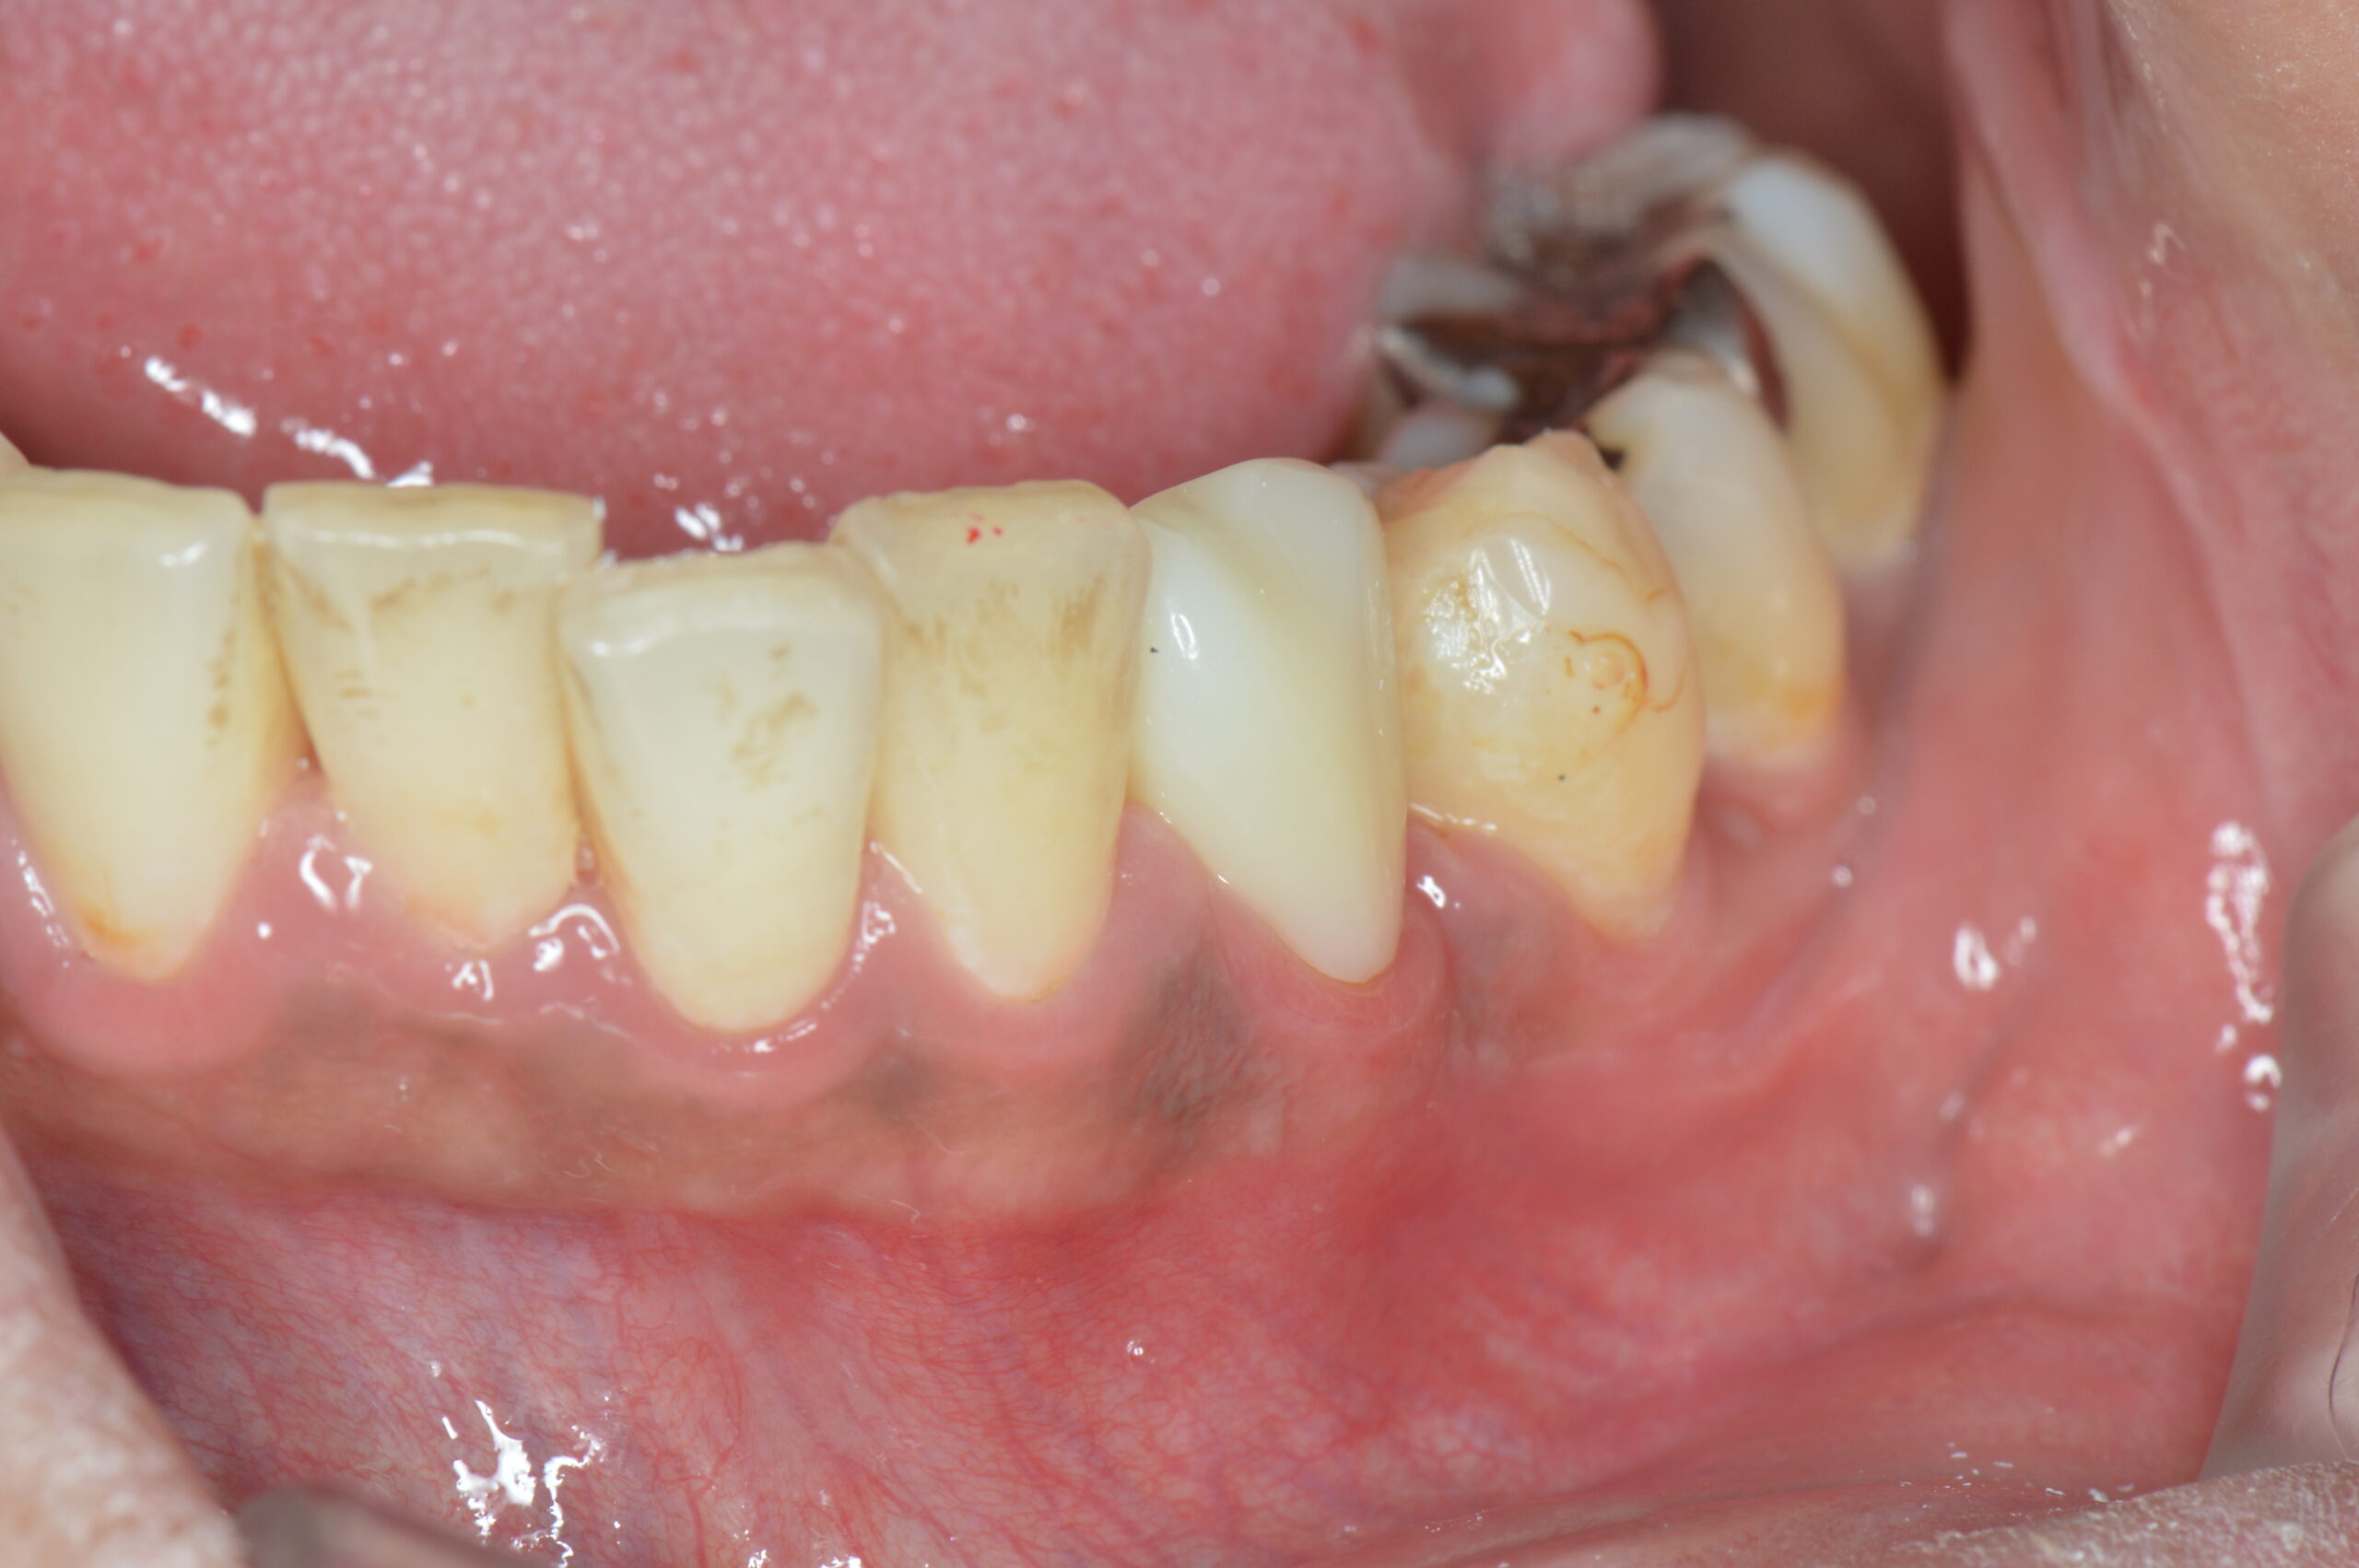

下の写真は、最終的なクラウン(被せ物)を装着した状態です。歯肉の腫れもなく、歯茎のラインも自然な位置に落ち着いています。機能的にも審美的にも良好な仕上がりとなりました。